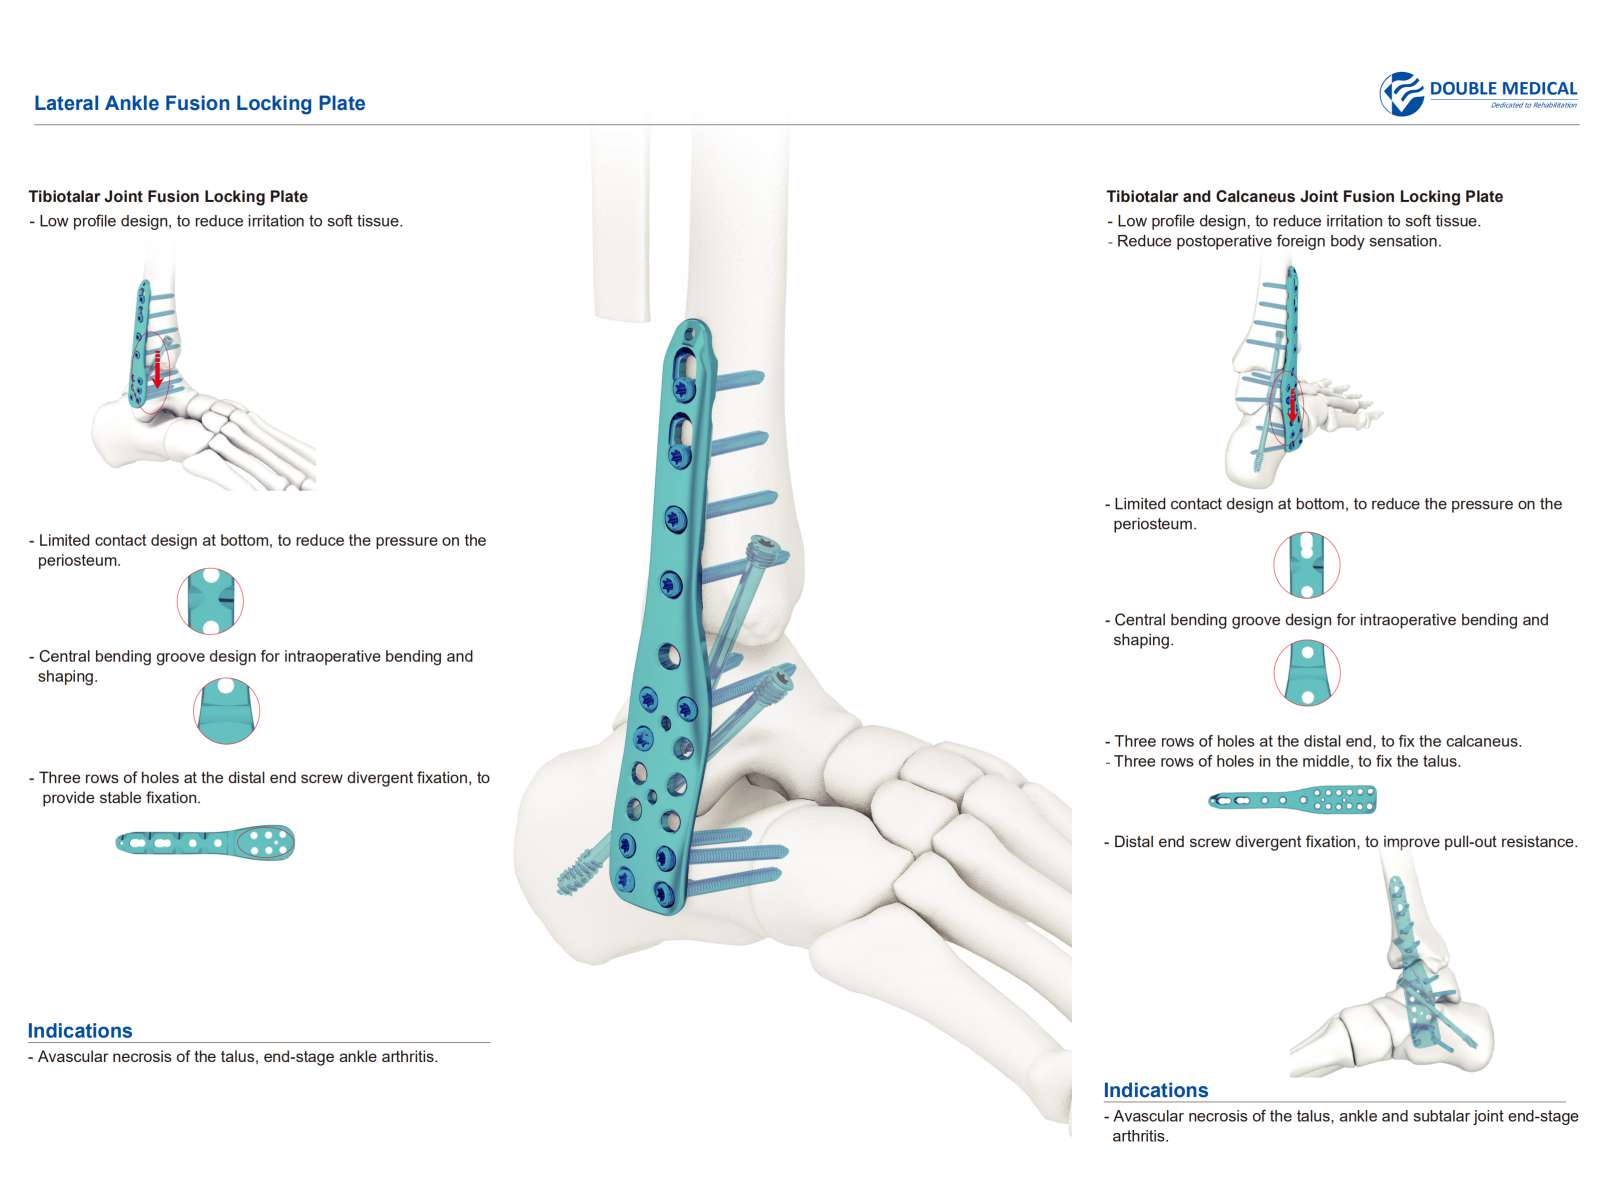

Características:

- Tres filas de orificios en el extremo distal, para fijar el calcáneo; Tornillo de fijación divergente, para mejorar la buena sujeción.

- Tres filas de agujeros en el medio, para fijar el astrágalo; tornillo de fijación divergente, para proporcionar una fijación estable

- Diseño de perfil bajo, para reducir la irritación de los tejidos blandos.

Indicación:

- Fusión de la articulación tibiotalar

- Fusión de tibiotalar lateral y calcáneo